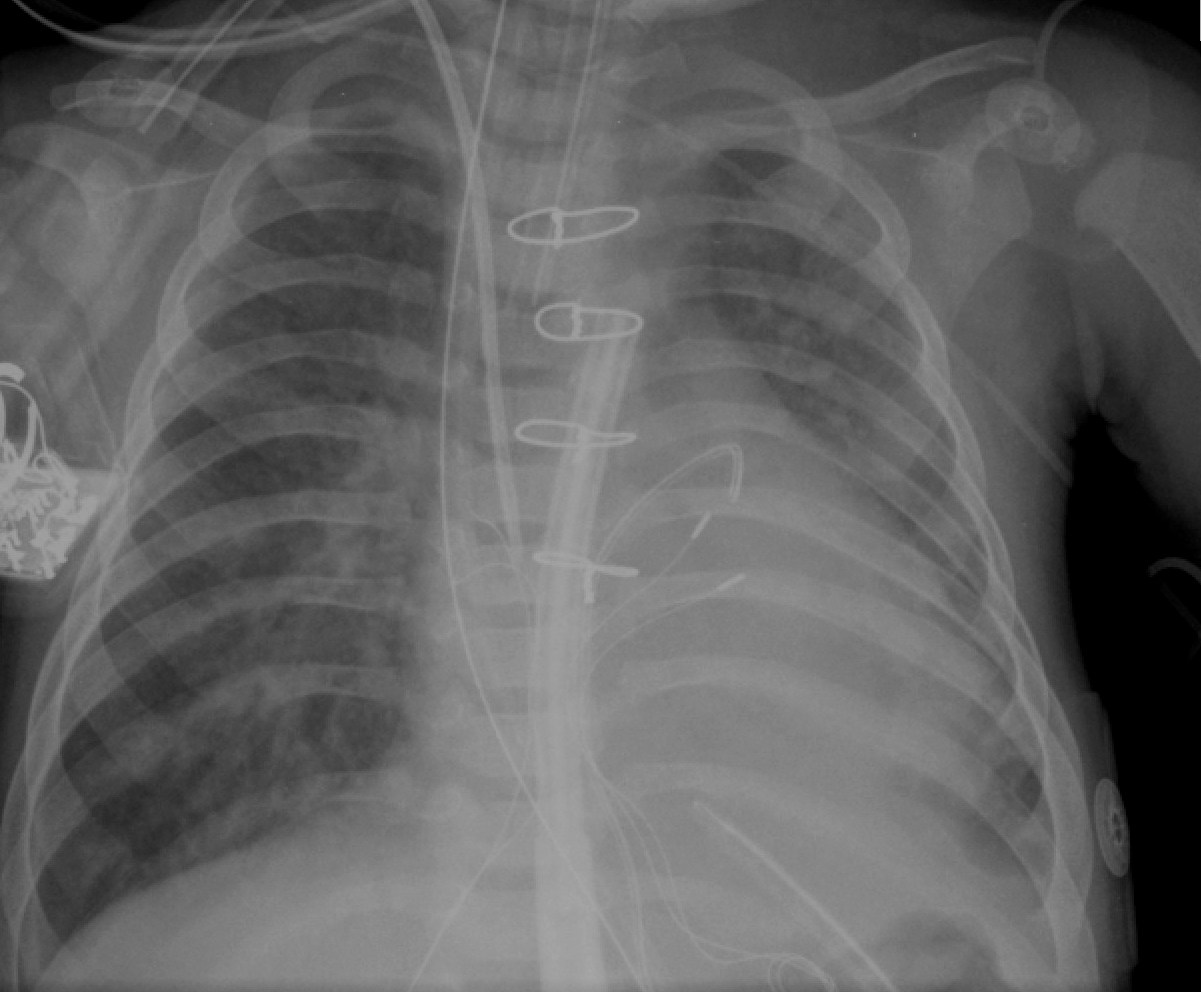

Answer: RV outflow tract.

Rationale: PA pressure has a ventricular trace with a pressure of 55/1. If you enlarge and see, pressure trace is typical of a ventricular pattern. So, the line tip is in the RV. But, in the CXR, it is high up in the RV. Combining the two findings, the line tip has to be below the valve i.e. RVOT.

Of course, this patient has elevated PA pressure at ~50% systemic level.